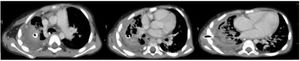

A chest CT scan was performed 24 days after admission to the ICU (Fig. 1) that revealed necrotizing pneumonia with signs of a probable bronchopleural fistula. The patient improved progressively, and a tracheostomy could be performed 1 month after admission. Invasive ventilation was disconnected on day 45, but the air leak through the chest tube persisted.